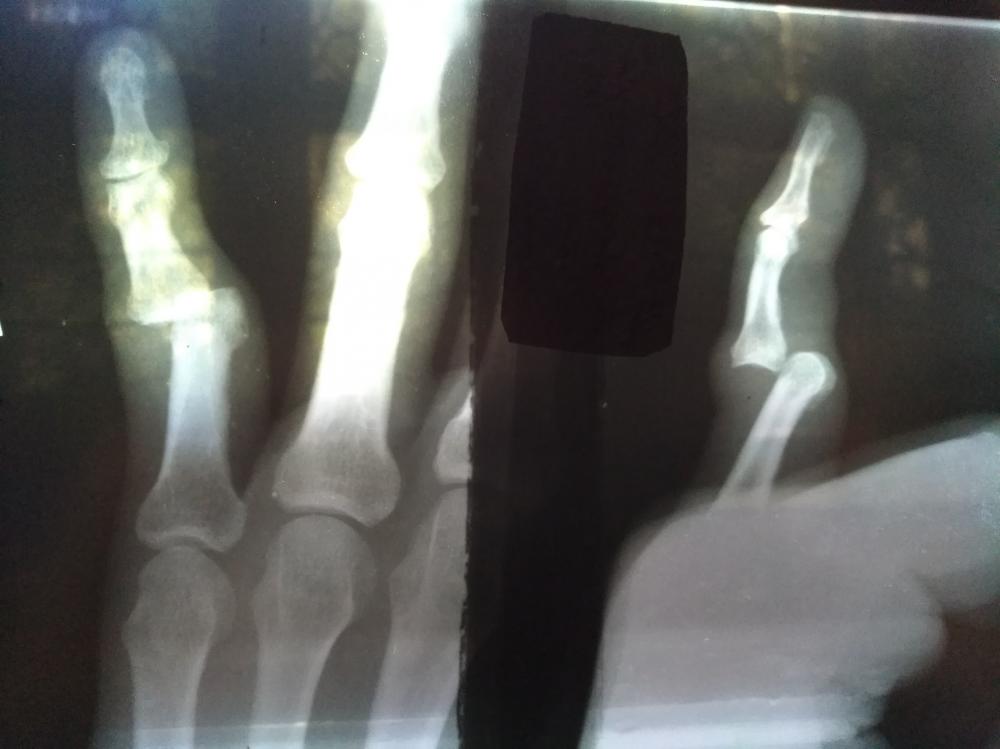

Почти 4 года назад. Не нога, но приятного мало. Смотришь и думаешь - что-то тут не так. Боль терпимая. Сам себе хотел вправить. Вывих, разрыв суставной капсулы. Другой врач потом ещё и перелом какой-то увидел.

IMG_20171102_150406.jpg